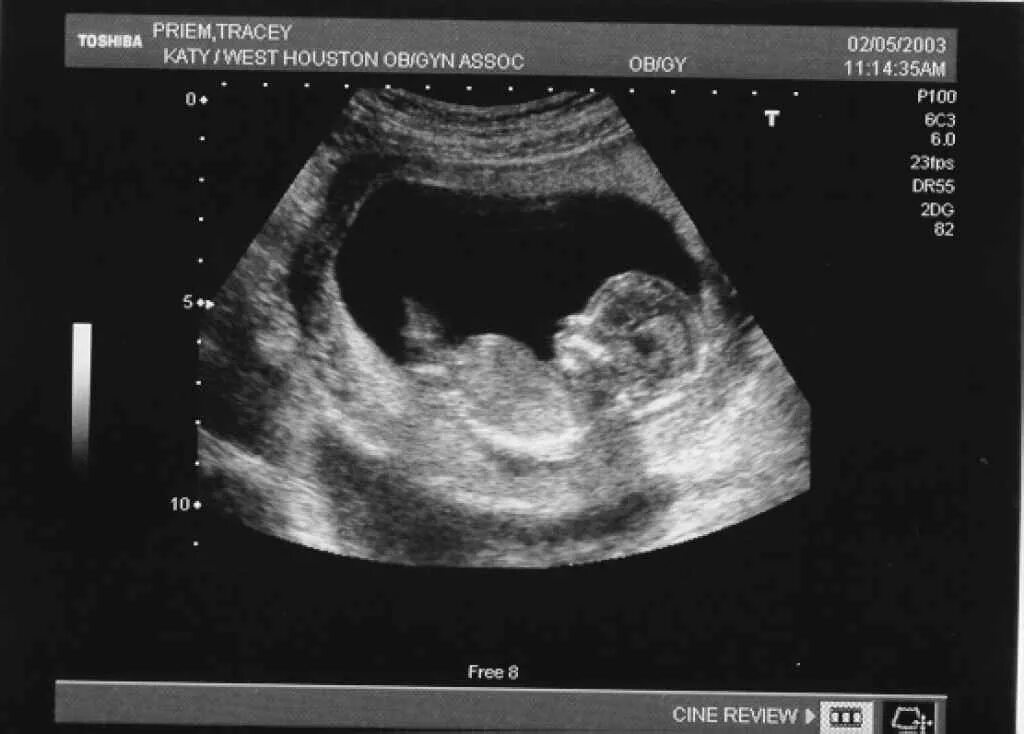

12 неделя беременности ощущения в животе